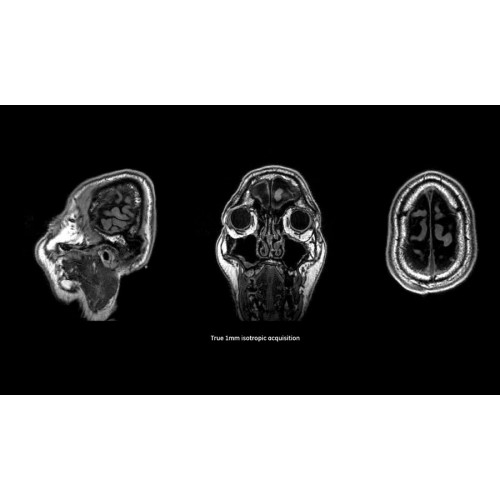

МРТ-аппараты, Полуоткрытые аппараты МРТ, МРТ аппараты для животных